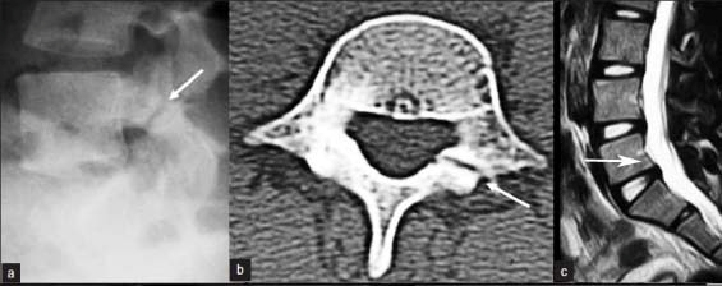

2. Истмический спондилолистез (спондилолиз)

Слабость суставных отростков, которая может быть результатом их перелома (чаще в детстве или подростковом периоде) ведет к соскальзыванию вперед вышележащего позвонка. Это наиболее часто выявляемый листез среди молодых, обычно встречается на уровне L5-S1, ведущий к компрессии нервных структур разросшейся соединительной тканью в месте перелома. Некоторые авторы считают причиной развития истмического листеза не однократную травму, а повторяющуюся много раз. Большинство пациентов с истмическим листезом не достигают высоких степеней соскальзывания позвонка и долгое время не предъявляют жалоб на боли.

Рис.3a,b,c. Истмический спондилолистез (спондилолиз). a) Рентгенограмма поясничного отдела позвоночника. Стрелкой указана зона дефекта (спондилолиза) дужки L5 позвонка. b) Компьютерная томограмма (КТ) L5 позвонка. Стрелкой указана зона дефекта (спондилолиза) дужки L5 позвонка. с) Магнитно-резонансная томографи (МРТ) поясничного отдела позвоночника. Стрелкой указано смещение L5 позвонка кзади I степени.Рис.3a,b,c. Истмический спондилолистез (спондилолиз). a) Рентгенограмма поясничного отдела позвоночника. Стрелкой указана зона дефекта (спондилолиза) дужки L5 позвонка. b) Компьютерная томограмма (КТ) L5 позвонка. Стрелкой указана зона дефекта (спондилолиза) дужки L5 позвонка. с) Магнитно-резонансная томографи (МРТ) поясничного отдела позвоночника. Стрелкой указано смещение L5 позвонка кзади I степени.